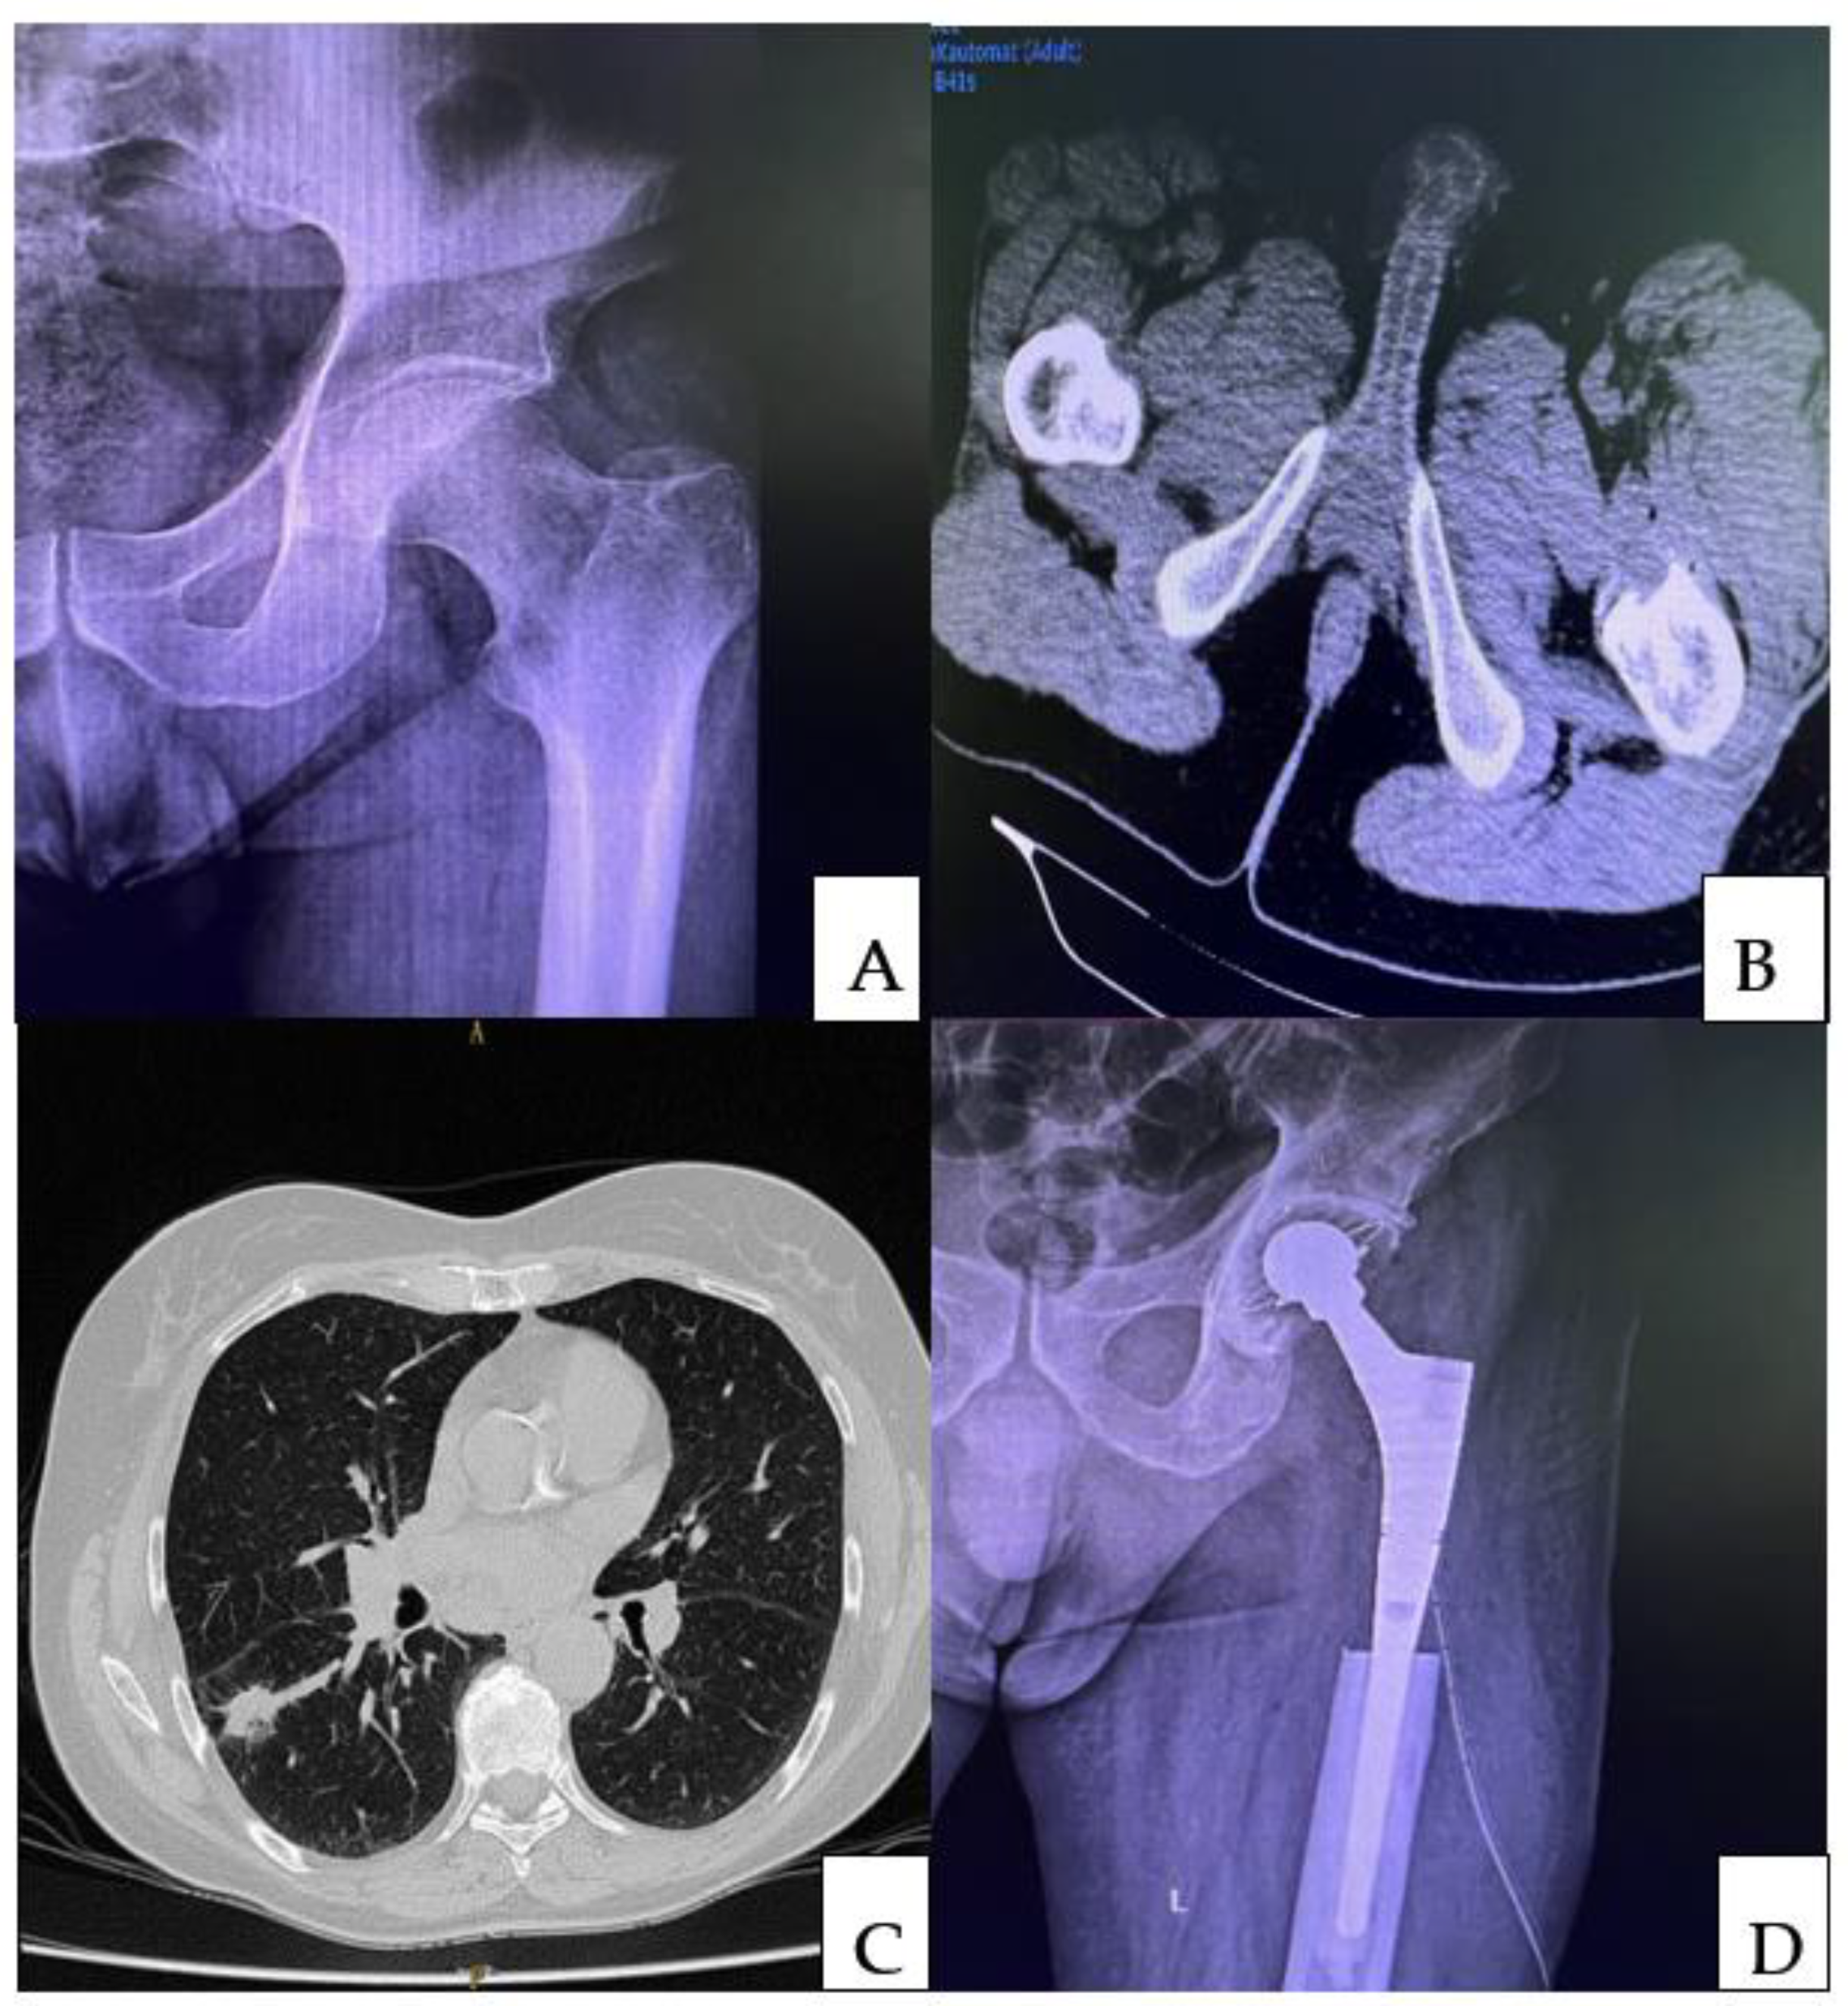

5.3. Treatment of Complete or Impending Fractures in Unique Bone Metastasis following Lung Cancer—Resection Followed by Intramedullary Nails and Acrylic Bone Cement